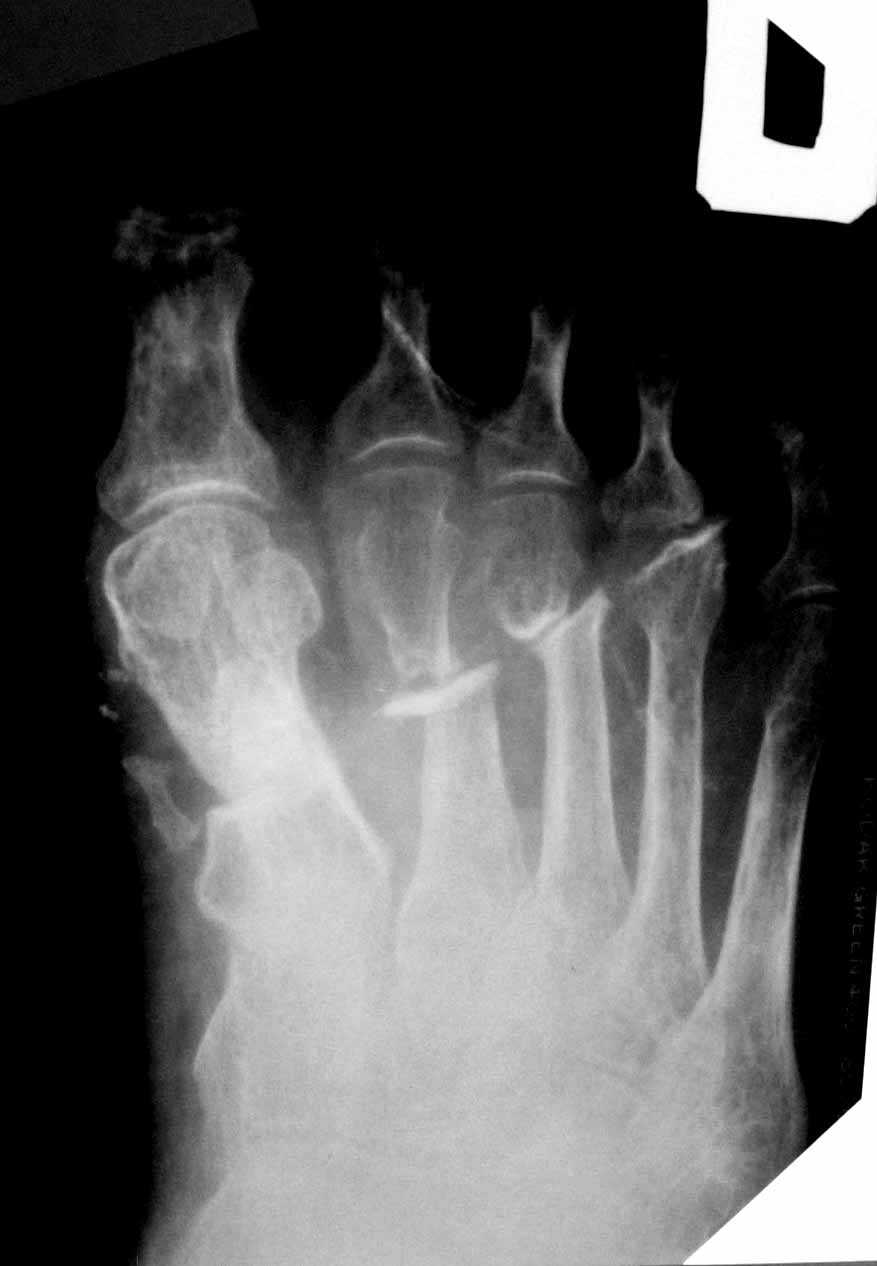

5 месяцев после тяжелой открытой травмы стопы Обратился иногородний пациент 56 лет с ложным суставом плюсневых костей после открытого перелома. Имеется латентная инфекция-свищ закрылся месяц назад, умеренная отечность, плотные рубцы на тыле стопы, подвижность в ложных суставах незначительная, опороспособность стопы страдает.Как лучше взяться за лечение? Есть мысли о дистракции в аппарате. Высок риск через рубцы открывать линию перелома. Кто сталкивался с подобным?

Снимок, выложенный на форуме, единственный. Пациент был лишь один раз на приеме. Плотные рубцы на тыле стопы, спаянные с сухожилиями разгибателей, свищ открывался в области головки 3 плюсневой кости.признаков нарушения кровообращения нет.Теоретически добраться с аккуратной препаровкой до ложных суставов 2-3 плюсневых костей можно, стабилизировать минипластинами с декортикацией, но всем известно плохое заживление в этой зоне.